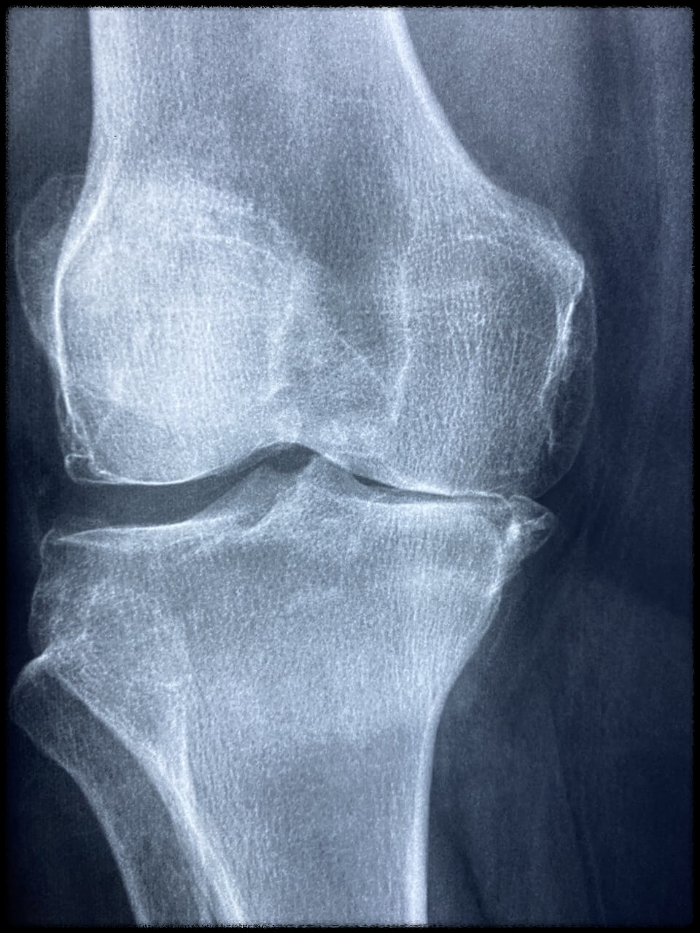

- 살면서 가장 많이 사용되는 곳 중 하나인 무릎은 몸무게를 지탱하기 위해 많은 에너지를 소모하지만, 노화가 진행

되면서 무릎에 있는 연골이 닳게 됩니다. 그로 인해 뼈와 인대에 손상이 생기기도 하고, 무릎에 염증이 생기면서

통증이 생기는 것을 퇴행성관절염이라고 하며, 퇴행성관절염이 악화가 되면 무릎관절수술을 진행하게 됩니다.